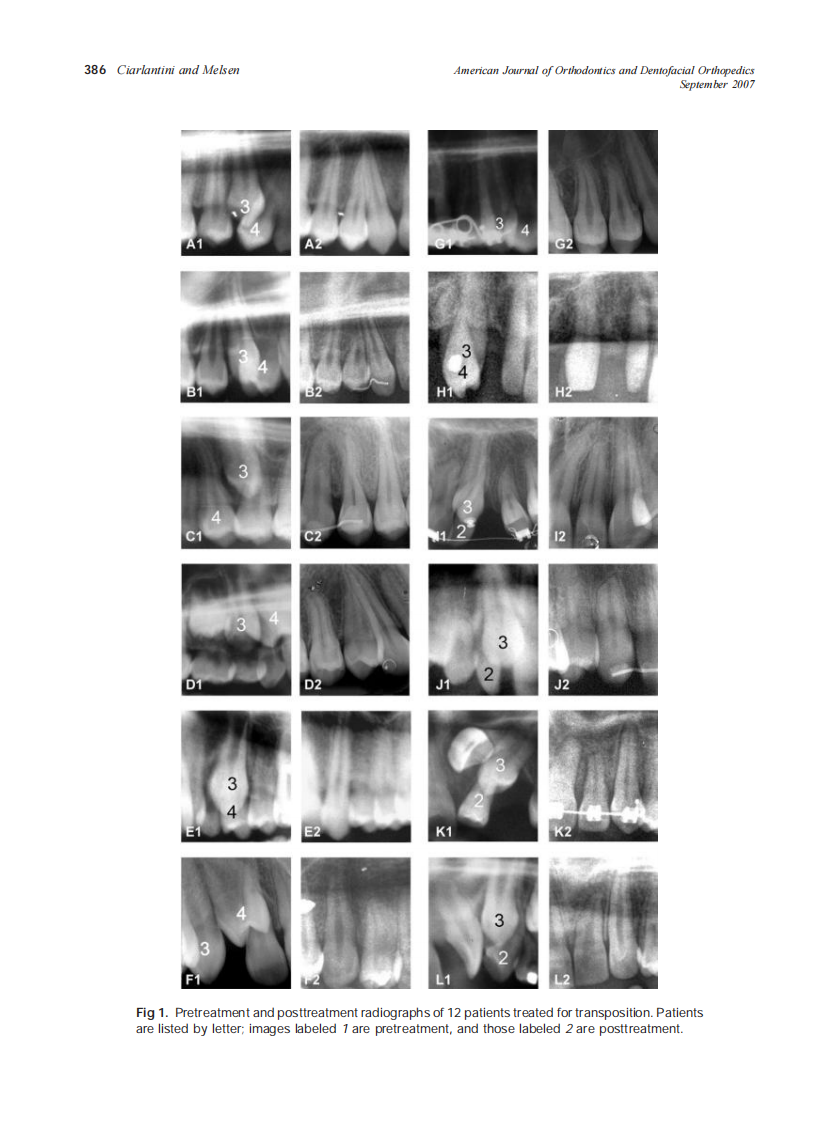

2007_132_3_385_394_Ciarlantini.pdf